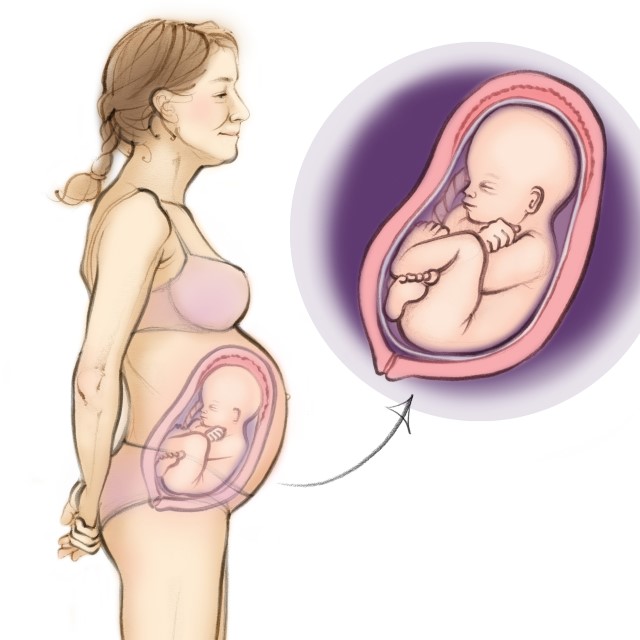

Baby Born at 30 Weeks Your 30 Week Preemie Peanut 2024, Family Stories Miracle Babies 2024, Born at 30 weeks and weighing 3 lbs our son has defied expectation 2024, My 30 weeker Lisa s story Bliss 2024, I Was Only 30 Weeks And My Baby Wasn t Ready To Come Yet 2024, Greta s NICU Story Born at 30 weeks 2024, My 30 weeker Lisa s story Bliss 2024, A 10 day old premature baby born at 30 weeks Stock Photo Alamy 2024, Family Stories Miracle Babies 2024, Having my daughter at 30 weeks has changed me as a person Tommy s 2024, Miracle baby born with NO SKIN and 30 weeks premature defies all 2024, World Prematurity Day Julen and Carla tiny twins born at 30 weeks 2024, A premature baby born at 30weeks and a day hours after birth 2024, Miracle baby born with NO SKIN and 30 weeks premature defies all 2024, Little Albie pregnant 30weeks 30weeksgestation 2024, Family Stories Miracle Babies 2024, Smiling Baby Gives Hope to Parents of Preemies 2024, World prematurity day Giving birth to preemie in 30 weeks of 2024, Woman gives birth to baby at 30 weeks after being diagnosed with 2024, My Strong Little Journey Jess Xander Jake Twins at 30 weeks 2024, Grace 11 days old 30 week preemie Preemie babies Preemie 30 weeks 2024, Exactly 30 weeks at birth Moms of Preemies Forums What to Expect 2024, Baby born weighing 11oz believed to be UK s smallest premature baby 2024, My 30 weeker Lisa s story Bliss 2024, Warm Baby Project My little girl born at 30 weeks weighing 2lb 2024, My NICU babe born at 30 weeks now 35 1 and the awesome onesie 2024, 30 Weeks Pregnant Symptoms and Baby Development Pampers 2024, 30 weeks pregnant Pregnancy articles support NCT 2024, Baby Girl was born at 30 weeks July 2018 Babies Forums What 2024, Miracle baby born at 23 weeks weighing less than a bag of rice is 2024, Parents of premature baby born 12 weeks early happy he s home 2024, Premie Baby 30 weeks BabyCenter 2024, fr Paddy on X 2024, Mater s smallest baby a Christmas miracle this year Mater Mothers 2024, Birth story Preemie Twins born at 30 weeks NICU Palms to Pines 2024.